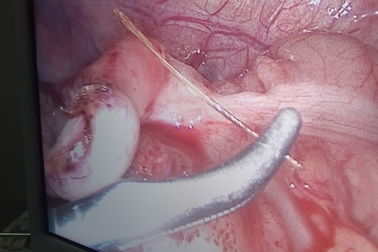

Mục sở thị quá trình lấy xương cá dài 4cm đâm thủng ruột nonMột bệnh nhân 48 tuổi quê ở Vĩnh Long bị xương cá đâm thủng ruột non vừa được các bác sĩ khoa Ngoại tổng hợp Bệnh viện Đa khoa TP Cần Thơ mổ nội soi ổ lấy ra một xương cá dài 4cm.